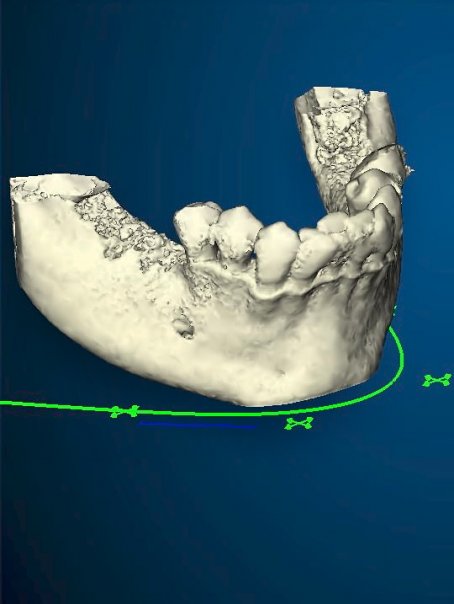

3d Positioning Of The Implant On The Lower Jaw

Guided Surgery Planning